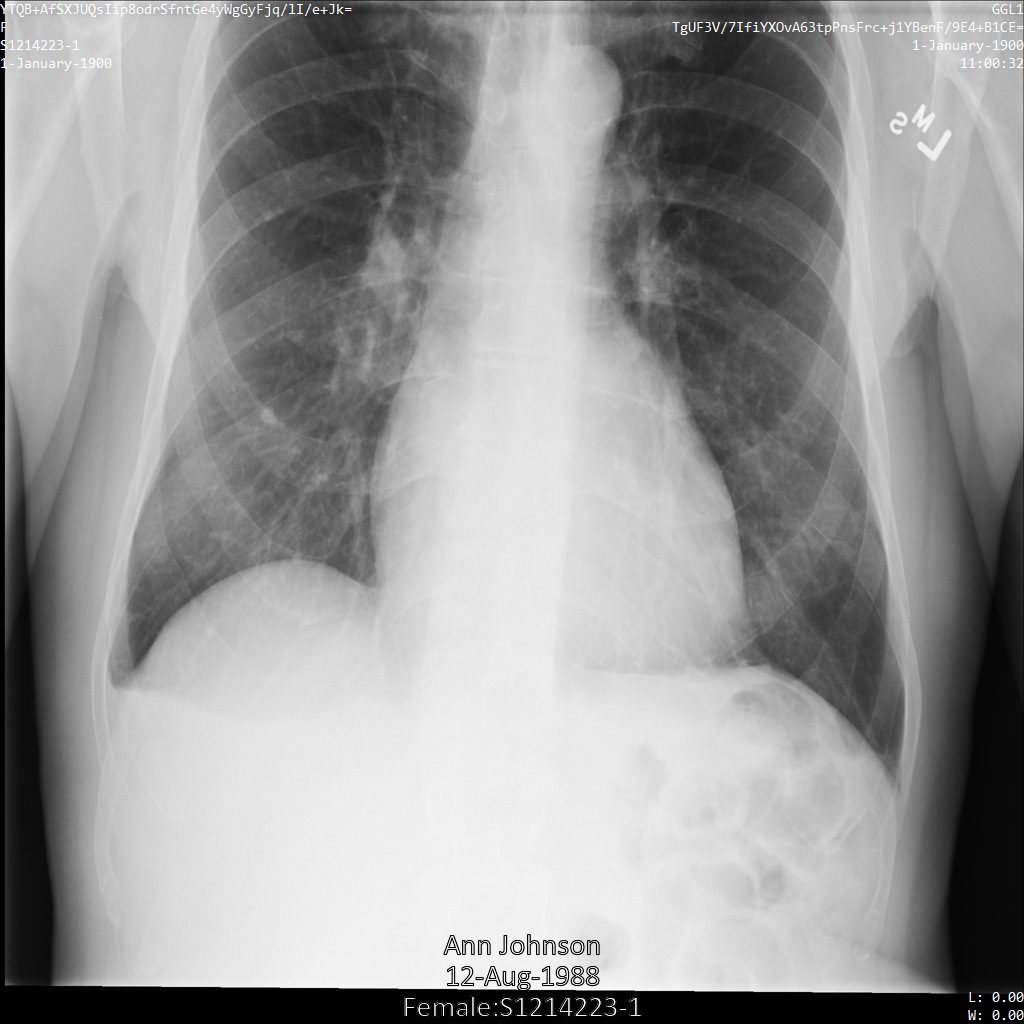

En la siguiente imagen, se muestra una radiografía sin ocultamiento de un paciente:

Después de enviar la imagen a la API de Cloud Healthcare mediante la opción REDACT_SENSITIVE_TEXT, la imagen aparece de la siguiente manera:

Puedes ver que ocurrió lo siguiente:

- Se ocultó el elemento

PERSON_NAMEen la esquina inferior izquierda de la imagen - Se ocultó el elemento

DATEen la esquina inferior izquierda de la imagen

El sexo del paciente no se ocultó porque no se considera texto sensible de acuerdo con los Infotipos de DICOM predeterminados.